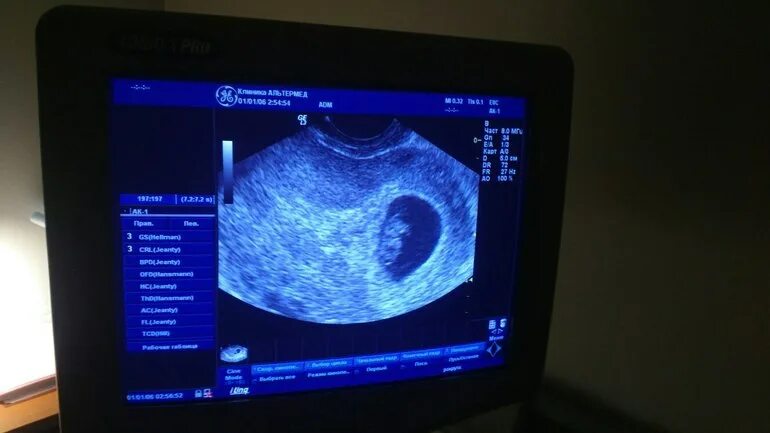

Узи 6 месяцев